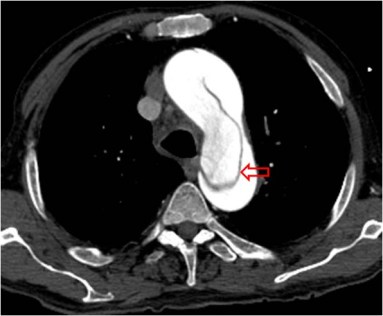

SIGNO DE LA AORTA PEQUEÑA

Signo de hipovolemia en la TC abdominal. Corresponde a vasoconstricción extrema de la aorta (flecha roja) como mecanismo que trata de compensar la hipovolemia que se ve en pacientes politraumatizados con grandes pérdidas hemáticas y en otras situaciones (shock séptico, cirugía, parada cardiaca, reacción alérgica,…). Se define como un calibre aórtico menor de 1,3 cm tanto dos centímetros por encima de las arterias renales como 2 cm por debajo. El ejemplo corresponde a un paciente politraumatizado con un bazo roto (flecha blanca).

Este signo forma parte del complejo de hipotensión en CT, antes llamado shock intestinal. Este término se refiere a un grupo de hallazgos abdominales en pacientes con hipotensión severa. Incluye: engrosamiento de asas de delgado (> 3 mm), realce de las paredes o hiperdensidad comparada con el psoas, vena cava inferior plana, aorta pequeña, heterogenicidad del páncreas con líquido peripancreático (no unánimemente aceptado), escaso realce del bazo (subjetivo), escaso realce hepático (25 UH menor que el bazo) e hiperrealce suprarrenal bilateral (hallazgo común en niños, controvertido en adultos).

Otro ejemplo de aorta pequeña en otro politraumatismo. El contraste se introdujo por una vía femoral, de ahí el intenso relleno de la vena cava inferior.